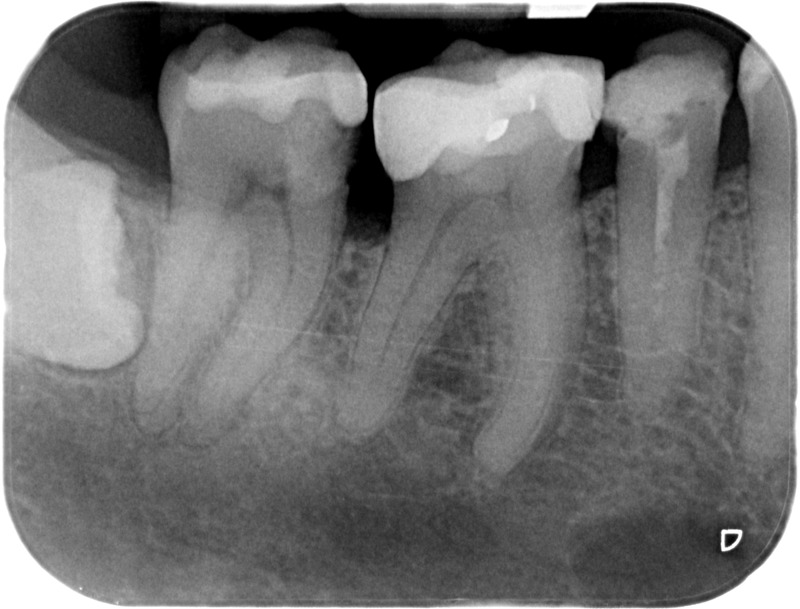

• Traitement endodontique : Sous anesthésie locale et à travers la protection d’un champ opératoire nous accédons à la pulpe de la dent à soigner, puis aux canaux de ses racines que nous devons désinfecter. Ce soin nécessite l’élimination complète de la source de contamination (souvent la carie) parfois sous une ancienne reconstitution ou une couronne qu’il faut alors retirer. Une fois le nettoyage et la mise en forme des canaux réalisés, nous les obturons de façon hermétique avec un ciment et un matériau thermoplastique appelé Gutta Percha. Ceci afin d’empêcher une nouvelle prolifération bactérienne et d’assurer le maintien de la dent dans ses structures de soutien (ligament parodontal et os alvéolaire). L’ouverture effectuée au centre de la dent sera d’abord refermée avec un pansement provisoire avant d’envisager ensemble la reconstitution d’usage : un composite, un inlay-onlay ou une couronne.

Avant